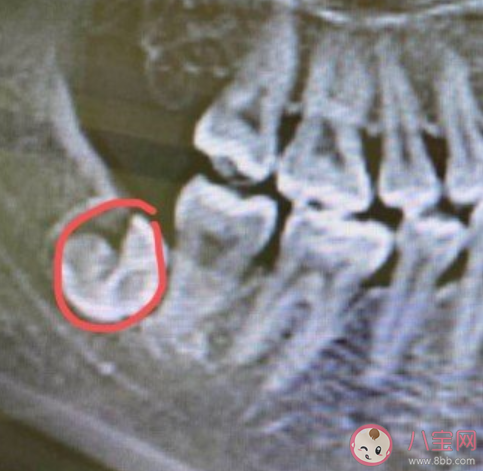

最后再举个反例,像下图这个:

智齿残余部分,体积很大,就是必须要清出来的。一般2mm是个界线,小于2mm我们就Let it go,任这一点点留在骨头里。